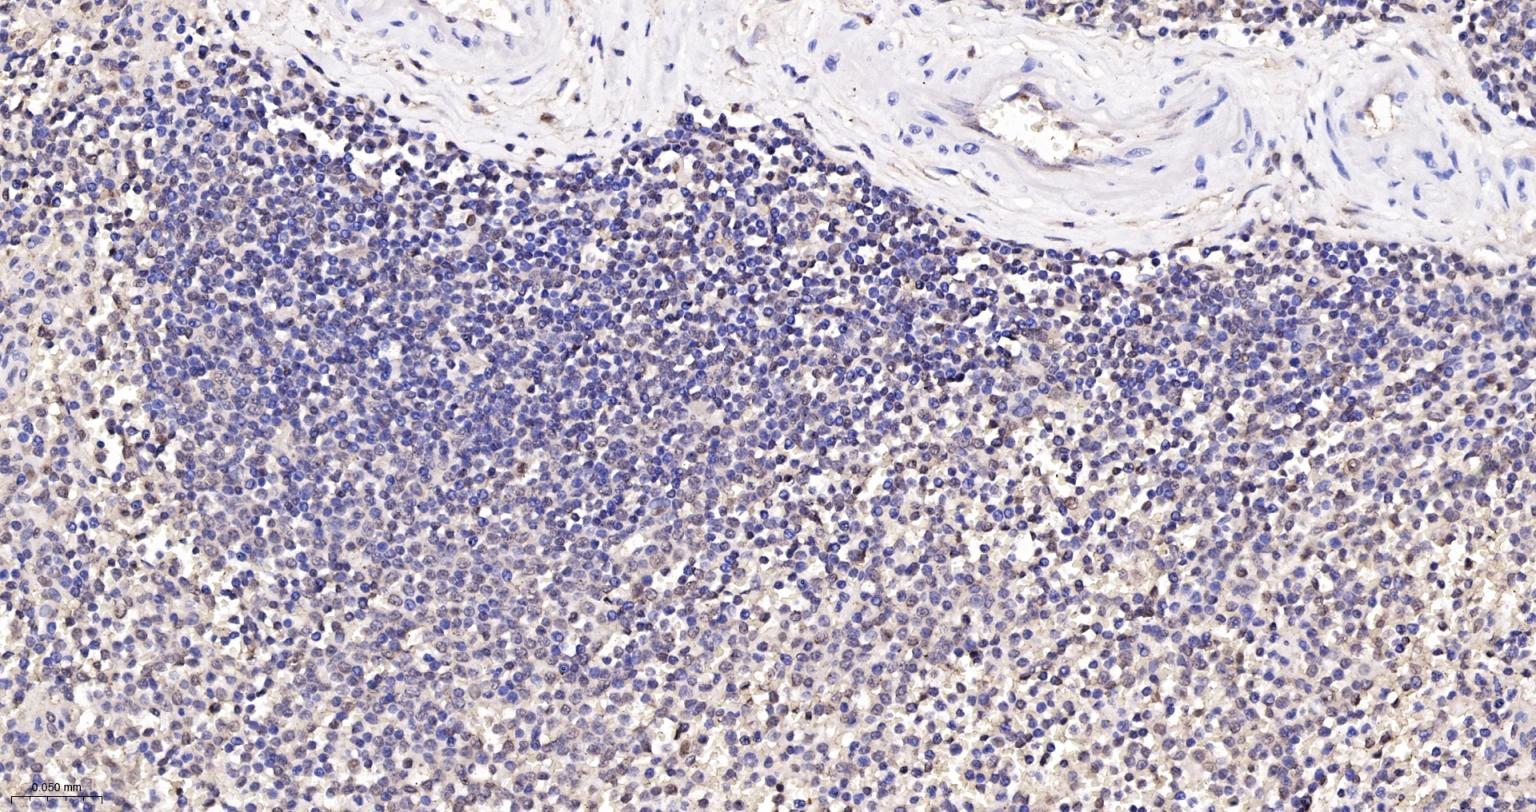

Paraformaldehyde-fixed, paraffin embedded Human Spleen; Antigen retrieval by boiling in sodium citrate buffer (pH6.0) for 15 min; The section was incubated with PSMB10 Monoclonal Antibody, Unconjugated (bsm-62964R) at 1:200 overnight at 4°C, followed by conjugation to the bs-0295G-HRP and DAB (C-0010) staining.